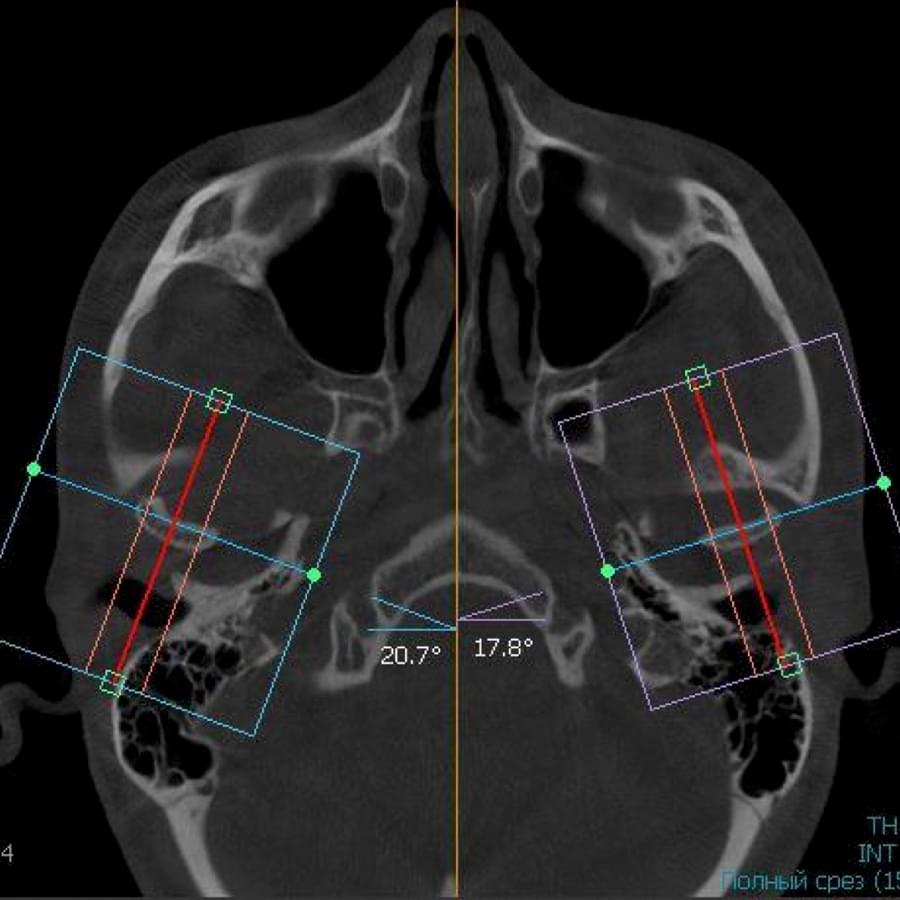

Отримайте вичерпну інформацію про стан ЛОР-органів завдяки надточній діагностиці на апараті

PLANMECA. Наші знімки дозволяють детально візуалізувати всі групи навколоносових синусів,

структури остіомеатального комплексу та анатомію носової перегородки.

Ми надаємо не просто знімок, а повний діагностичний сервіс:

Детальний опис: Кожне дослідження супроводжується професійним висновком лікаря-рентгенолога

з описом виявлених патологій (кісти, поліпи, сторонні тіла, рівень рідини, потовщення

слизової).

Зручна візуалізація: Можливість перегляду структур у будь-якій проекції (аксіальній,

корональній, сагітальній) для точної локалізації запального процесу.